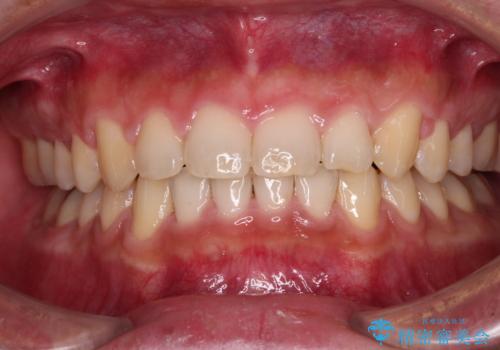

下の歯のがたつき 上より気になる

口元大事です! 見違える矯正!! 乱ぐい歯もあきらめないでください。